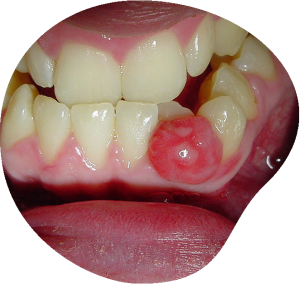

اگر بیماری لثه اولیه (جینجیویت) در درازمدت درمان نشود به بیماری پیشرفته…